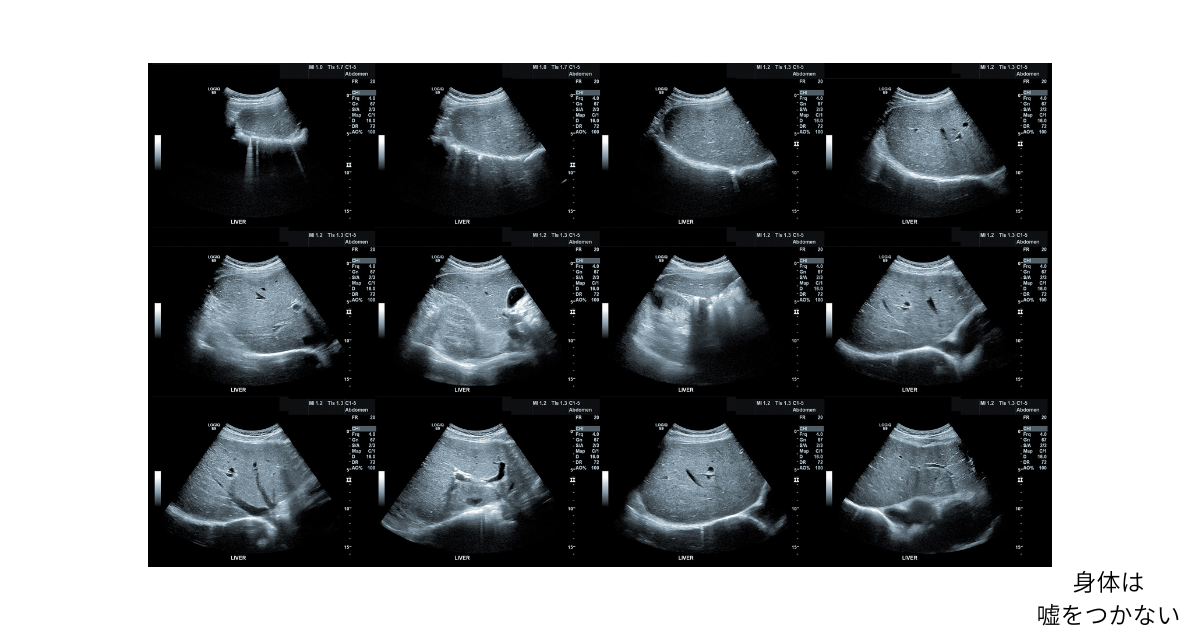

エコーで見えた「頑張りすぎ社員」の身体

そう話す社員の身体を、エコーで見たとき、

言葉とはまったく違う情報が映し出されることがあります。

しかし、エコーで見えてくるのは、

病気かどうかの二択だけではありません。

血流の変化。

臓器の動き。

緊張や硬さ。

エコーで身体を見ていると、

頑張りすぎている人に、

共通して見られる傾向があります。

しかしエコーには、

その“我慢の履歴”が正直に映ります。

エコーで見えていたような変化が、

ずっと前から積み重なっていたのです。

エコーで見える「頑張りすぎ」は、

社員個人を責める材料ではなく、

会社の状態を知るための情報です。